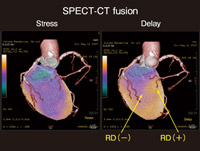

Amazon.co.jp: 心臓CTを活かす 新しい冠動脈疾患診断戦略。心臓CT実践ガイド | 診断と治療社。Vol.5 CTによる心臓検査の有用性と可能性。

Vol.5 CTによる心臓検査の有用性と可能性

Vol.5 CTによる心臓検査の有用性と可能性